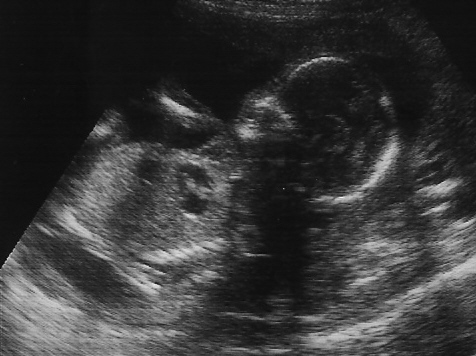

18-weeks